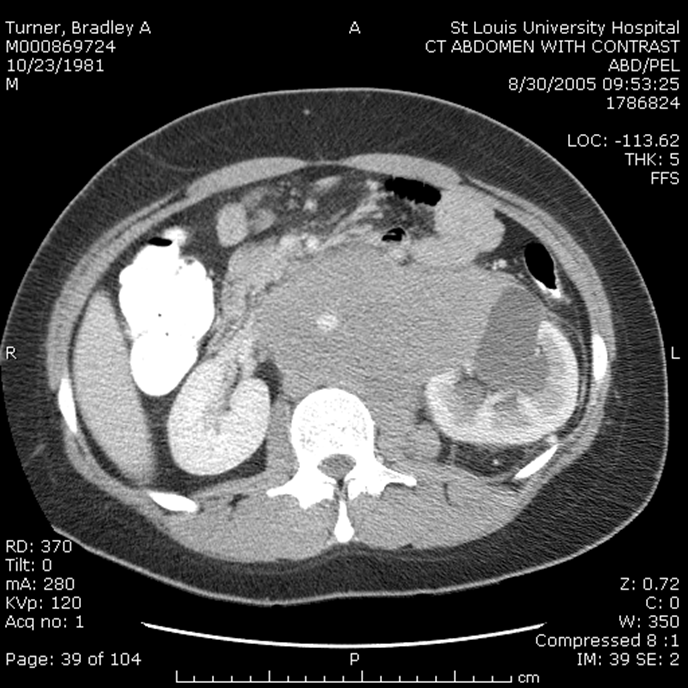

ā¢Ct Scan